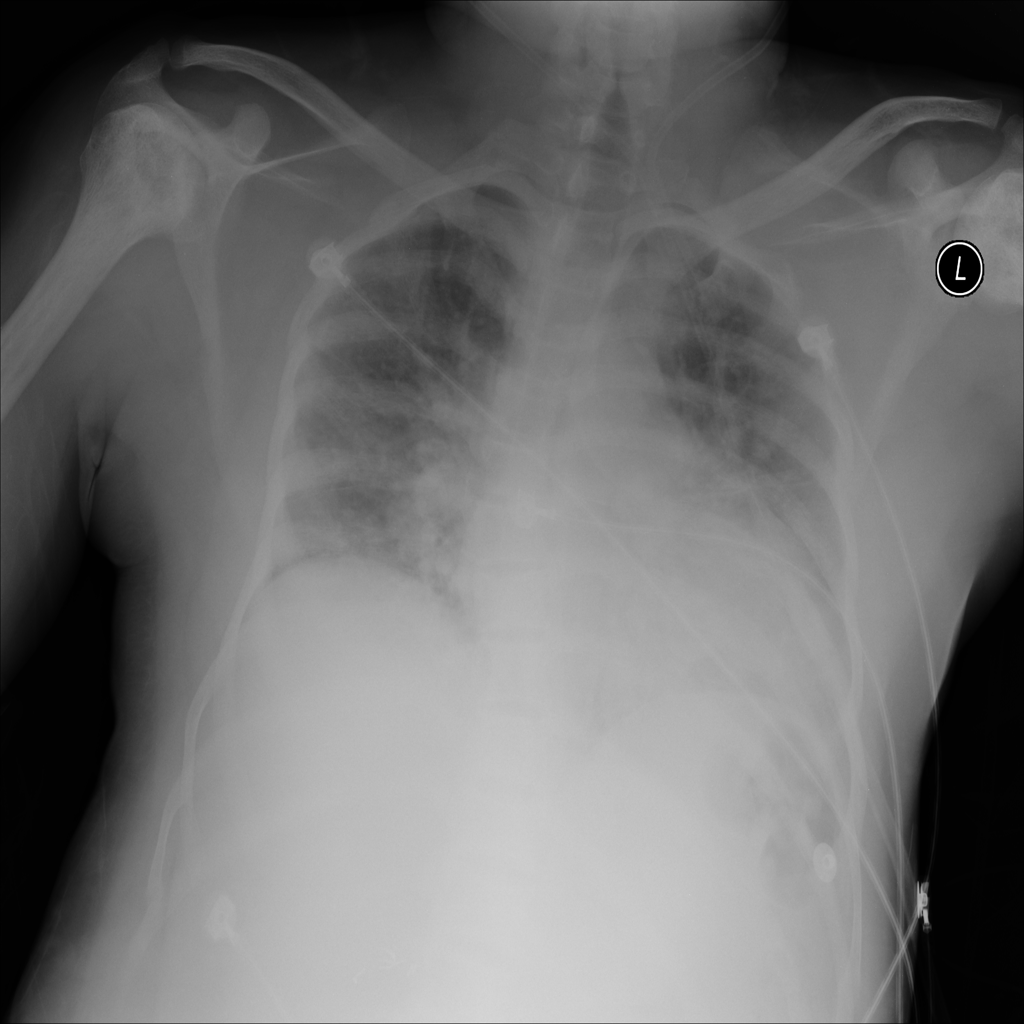

PAT-F3E7 · IMG-000Cardiomegaly

PAT-F3E7 · IMG-000

PA